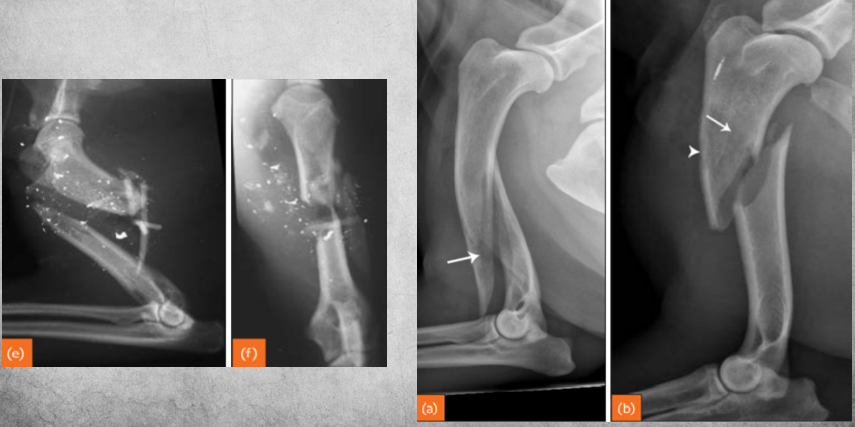

Fractures can be either..

A

primary or secondary.

Also, complete or incomplete. (periosteum can be intact with fracture line otherwise).

Left image: gunshot caused fracture.

Right image: osteosarcoma caused fracture.